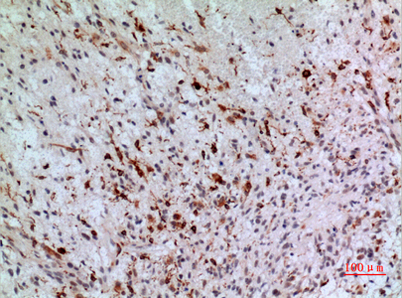

Product name: CD74 rabbit pAb

Dilutions: Western Blot: 1/500 - 1/2000. IHC-p: 1/100-1/300. ELISA: 1/20000. Not yet tested in other applications.

Immunogen: The antiserum was produced against synthesized peptide derived from the Internal region of human CD74. AA range:161-210